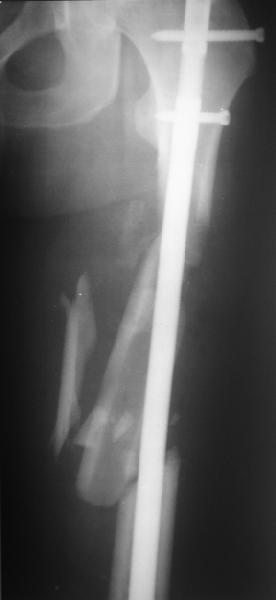

Уважаемые коллеги! От имени Алексея Смирнова всем спасибо за обсуждение. Больной прооперирован. Снимки в приложении.

Проксимальная и дистальная блокировка, независимо от техники введения штифта, ретроградно или антеградно, гарантирует сращение сегментарных переломов бедра без укорочения. Штифты диаметром 12 мм с блокировкой сверху и вниз двумя шурупами выдерживают вес 75 кг больного, что позволяет раннюю профилактику контрактур.

Погоня за "красивой рентгенограммой" не всегда оправдана для фиксации кости, где имеется массивное мягкотканое покрытие. Если так уж хочется исправить положение кости, то при наличии ЭОП, большие костные фрагменты могут быть развернуты или приближены к основному фрагменту методом применения Joystick.